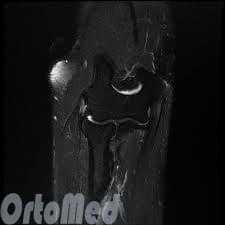

- МРТ. При помощи этого метода удается исключить наличие какого-либо другого недуга.

- МРТ: Для исключение другой патологии в сомнительных случаях, нередко выполняется магнитно-резонансная томография.